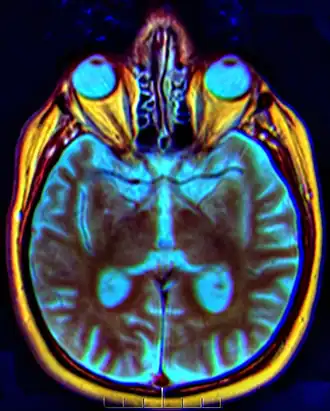

Het chiasma opticum[8] of kruising der oogzenuwen[9] is een vierkantig plat lichaam in de frontale kwab van de hersenen waarin de vezelbanen van de oogzenuwen elkaar kruisen.

De hoofdfunctie van het chiasma opticum is het beschikbaar maken van visuele informatie voor beide hemisferen. Prikkels vanuit de retina bereiken via de oogzenuwen het chiasma opticum en worden doorgestuurd naar een groep neuronen in de thalamus genaamd het corpus geniculatum laterale. Van daaruit vindt de verspreiding van informatie in het visuele hersengebied plaats.